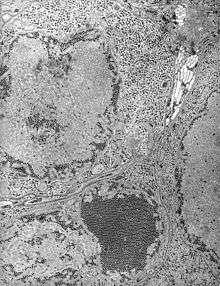

Human incidence of Saint Louis encephalitis in the United States, 1964-1998.

In the United States an average of 128 cases of Saint Louis encephalitis are recorded annually. In temperate areas of the United States, Saint Louis encephalitis cases occur primarily in the late summer or early fall. In the southern United States where the climate is milder Saint Louis encephalitis can occur year round.